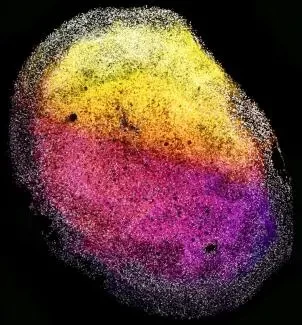

△ 一个完整的人类胎儿大脑器官的图像。干细胞用SOX2(灰色)标记,神经元细胞(TUJ1)根据深度用从粉红色到黄色的颜色编码。